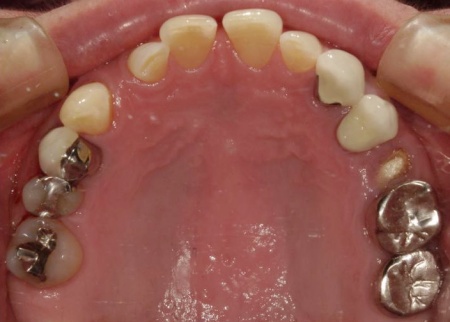

70代女性 歯根が割れた左下奥歯を抜きインプラントで噛み合わせを回復させた症例

レントゲン撮影を行って詳しく拝見したところ、左下奥歯(第1小臼歯)の歯根が割れていました。

まず、周辺組織に負担をかけないよう配慮しながら、慎重に左下奥歯(第1小臼歯)を抜きます。

抜歯後は骨や歯茎の回復を待ち、口腔内の状態が安定したことを確認して、インプラント埋入手術へ進みました。

後日、インプラントと骨がしっかりと結合したら、精密な型取りを行い、被せ物を作製します。

最後に完成した被せ物を装着し、痛みや違和感がないか、見た目や噛み合わせに問題がないかを確認して、治療を終了しました。